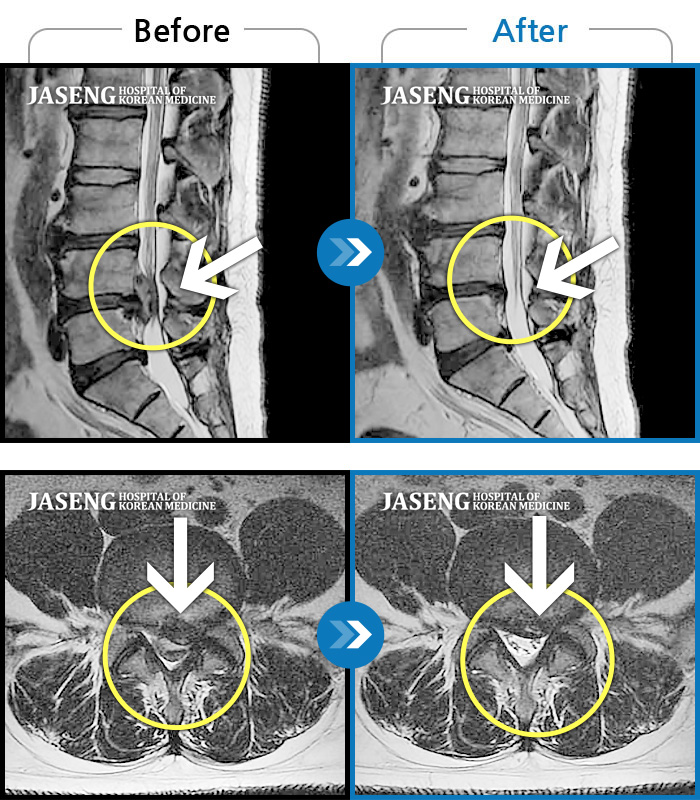

허리디스크

수원 · 김태성 원장

허리 통증과 우측 고관절~하지방사통이 심하여 활동하기 힘든 상태

촬영시기

2021.03.04 ~ 2021.10.06

2022.03.25